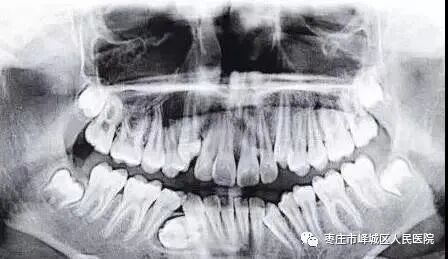

正畸治疗

众所周知,正畸治疗前对牙列的判断是影响治疗方案和最终效果的关键因因素。CBCT让我们在制订治疗方案前能清楚地评估牙根的方向及其与邻牙的关系,大大地提高了治疗方案的准确性,也避免了正畸不当导致牙根损伤的风险。